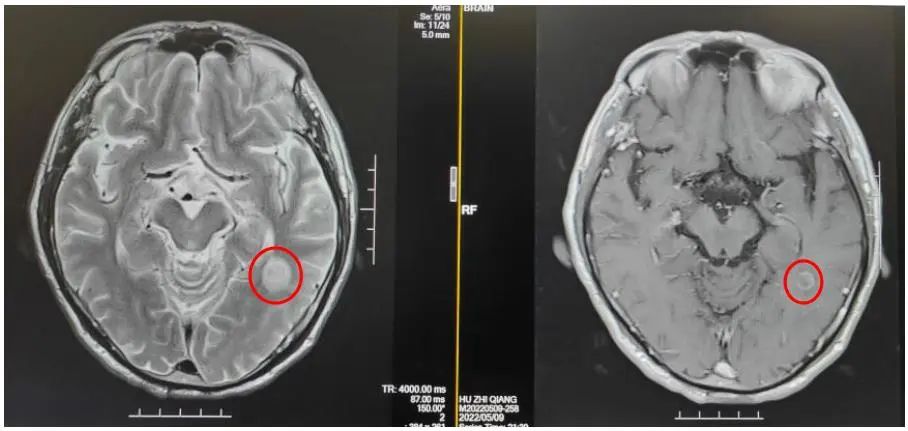

2022年5月9日MRI结果:左侧颞叶强化灶,考虑转移瘤。

2022年7月5日复查脑部MRI提示:与PACS20220529老片对比,现片示:左侧颞叶强化灶较前稍缩小。

MRI:与PACS20220529老片对比,现片示:左侧颞叶强化灶较前稍缩小。

该患者是一个基线伴有脑转移的广泛期小细胞肺癌患者,《2022年CSCO小细胞肺癌诊疗指南》推荐,对于无症状的脑转移小细胞肺癌患者,一线治疗推荐免疫联合化疗后,再行全脑放疗。此患者在进行4个周期斯鲁利单抗联合卡铂依托泊苷治疗后,影像学提示病灶明显退缩,脑转移病灶也明显缩小,疗效达到PR,充分证明斯鲁利单抗在广泛期小细胞肺癌患者中的良好疗效。